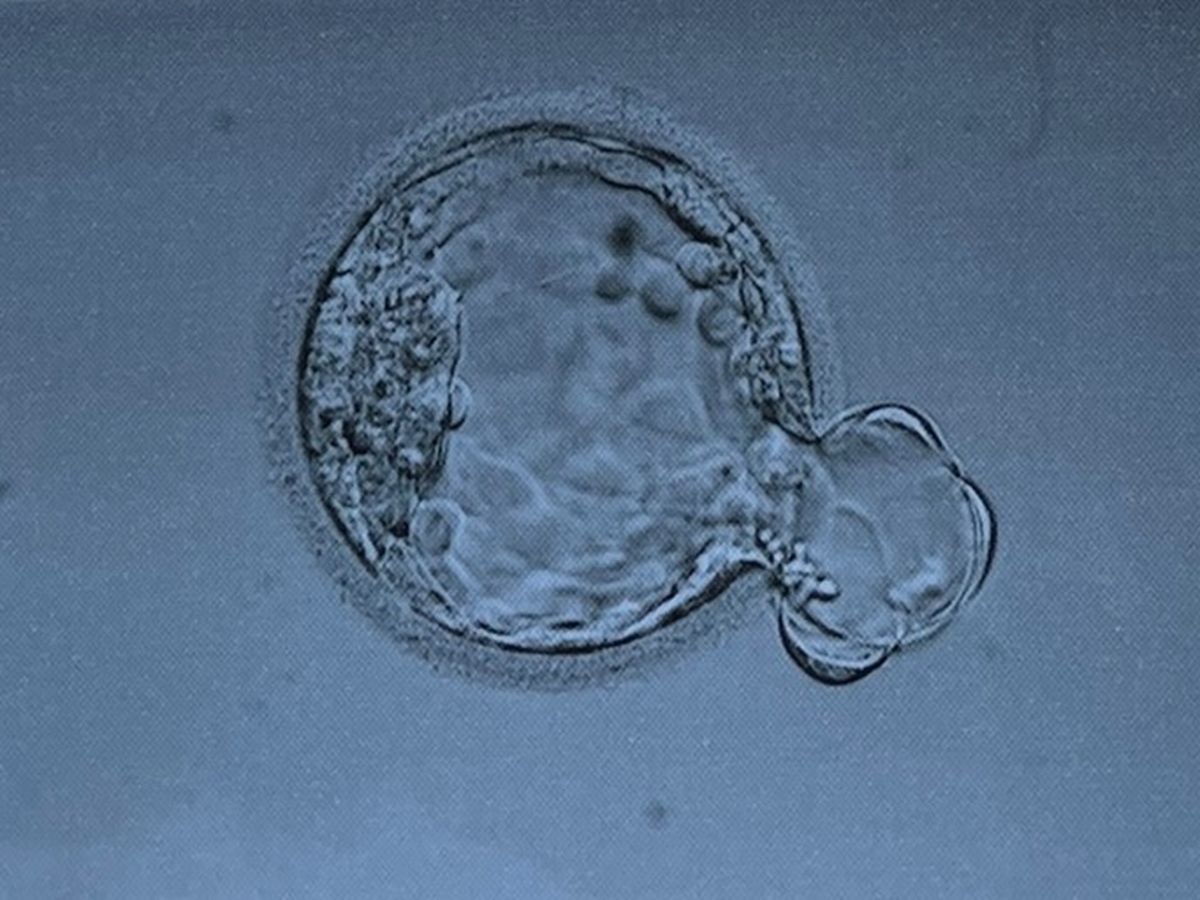

Due to the recent legislation that was passed in Alabama, all IVF procedures have been cancelled at UAB. My sister was scheduled to transfer her second embryo on March 20, 2024 in Birmingham but was informed that the transfer was canceled. Additionally, they are unable to have their embryo transferred out of state and need to find and hire a company to that is willing to accept liability during the transportation process. Heather has consulted a family law attorney and will be filing a petition with the Alabama Supreme Court to force UAB to release her embryo.

My sister and brother-in-law started IVF in December of 2020. Out of her two cycles, two embryos developed and were viable for transfer. My nephew Maximus was born in 2022 and without the wonderful Endocrinology and Infertility team at UAB my nephew would not be here today.